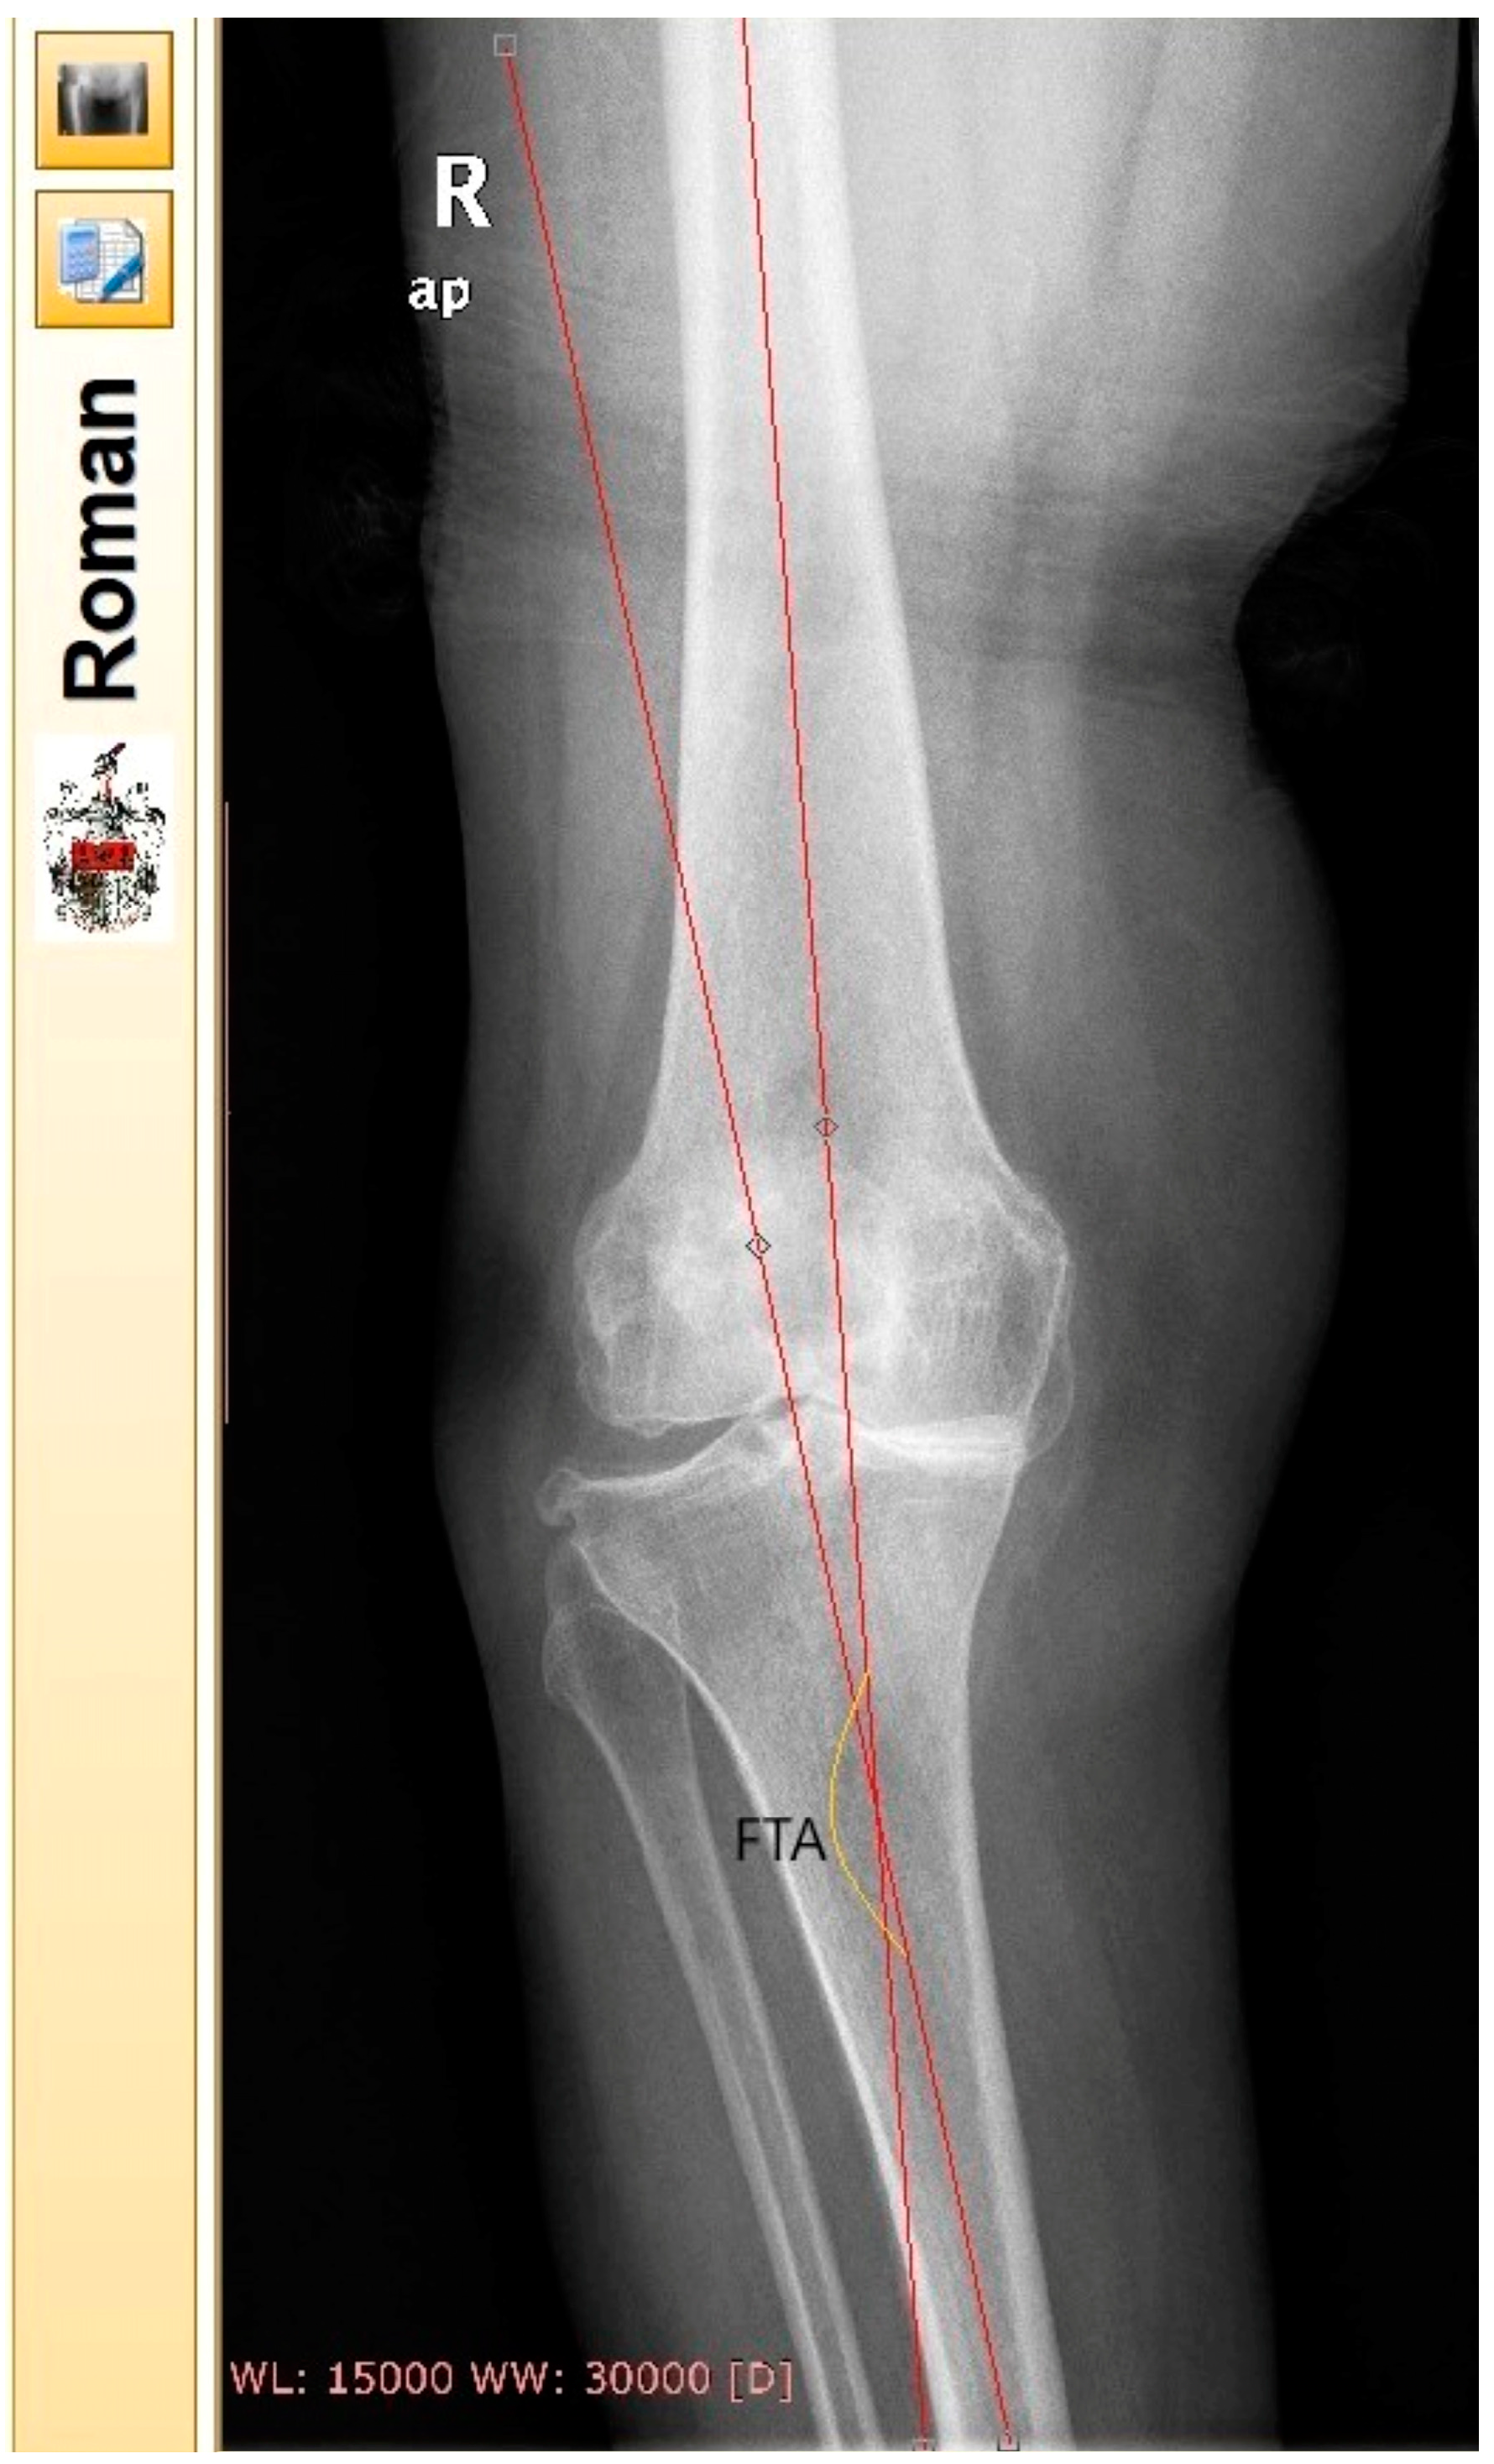

Preoperative KOA classification was performed by the surgeon who listed the patients for surgery. All patients underwent anteroposterior (ap) standing digital radiographs of the knee joints pre- and six months postoperatively (large film, 14 × 17 inch). FTA of the affected knee joint (AKJ) was measured according to Petersen and Engh [47]. Two independent blinded observers who did not participate in any other part of the study performed the FTA measurements. The sequence of X-rays and the file names were randomly generated. Same measurements were repeated by the observers with an interval of 15 days for both radiological assessments (pre- and six months postoperatively). The reported FTA pre- and postoperatively was calculated as the average of observers’ measurements. For the measurement of FTA, Roentgen Monographic Analysis (RoMAn) [48,49] free-to-share software version V1.70 was used (Robert Jones and Agnes Hunt Orthopaedic Hospital) (Figure 1). Each knee was categorized pre- and postoperatively as varus (VR), valgus (VL), or neutral (N) [50,51]. N knees were characterized as the ones with an FTA between 172.8° and 177.6°, VR as the ones with FTA > 177.6°, and VL knees as the ones with FTA < 172.8.

Figure 1. FTA measurement in the environment of Roentgen Monographic Analysis (RoMAn) free-to-share software version V1.70. The femoral anatomic axis was drawn by locating the midway between the femoral cortex in two points. The first one as far proximally as the radiograph allows and the second one 10 cm above the joint line. The same procedure was followed for the tibial axis. In this specific X-ray, FTA was calculated in a varus knee.